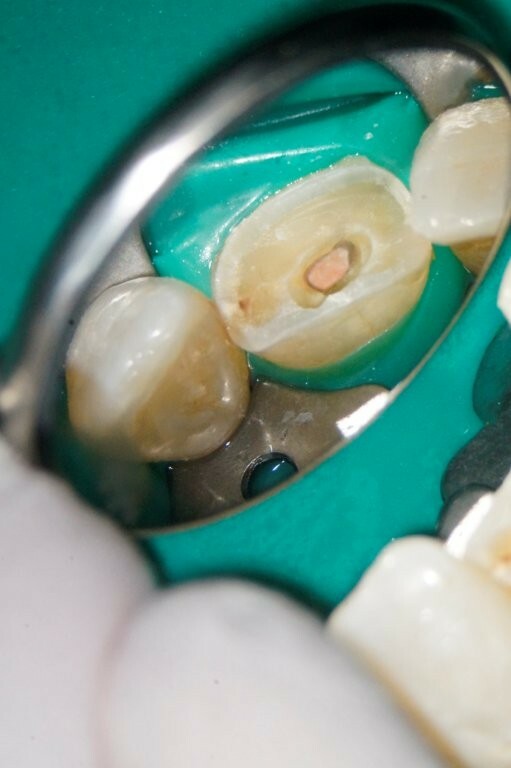

Guttapercha und AH Plus als Sealer. Anschließend wurden aufgrund der ovalen Kavität zwei Glasfaserstifte zur Stabilisation der Füllung eingebracht und mit Luxacore adhäsiv verklebt.